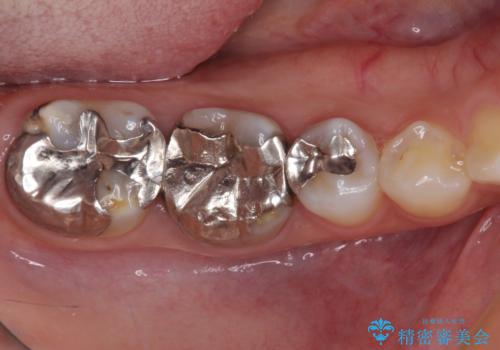

レントゲン写真などで診査した結果、奥歯の銀歯の下にはむし歯が多く存在し、右上の奥歯は歯根が破折していました。

銀歯の下のむし歯については、優先度の高い方からセラミッククラウンなどで治療していくこととしました。